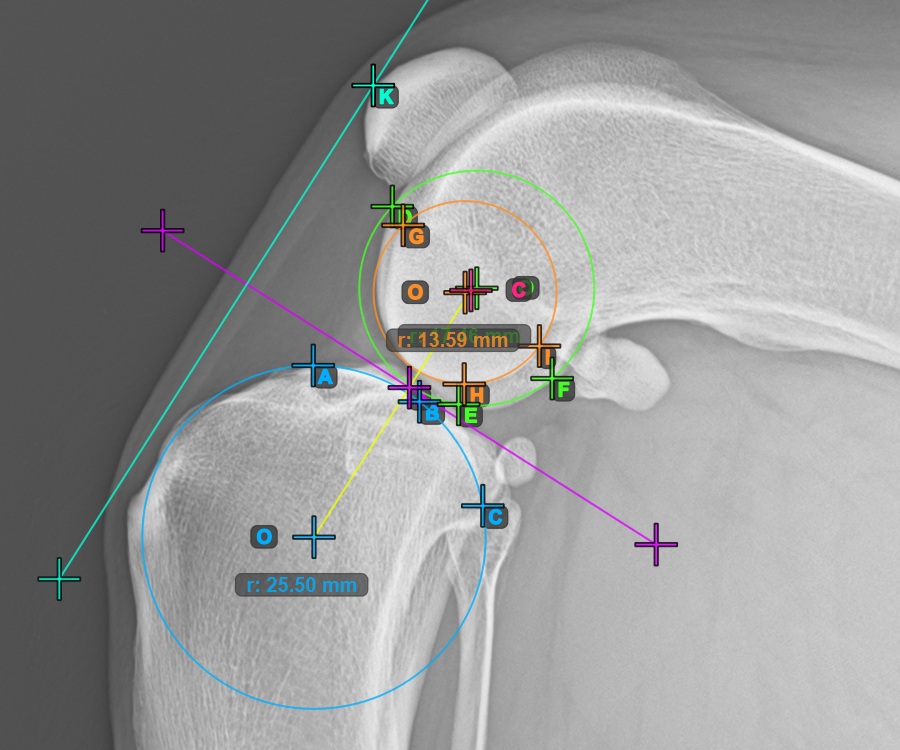

Jelölje meg a három pontot a combcsont fő condylusán (Condylus Femoris). A sorrendtől függetlenül ügyeljen arra, hogy megjelölje a legfelső pontot, a legalacsonyabb pontot és a Condylus Femoris középpontját. A három pont alapján a rendszer automatikusan létrehoz egy kört.

A lenti kép az első Condylus Femoris-on elhelyezett három pont tipikus elhelyezkedését ábrázolja.